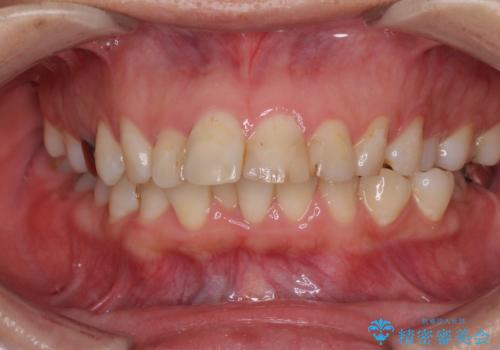

ハーフリンガル矯正による前歯部の叢生改善と口元の後退|上顎左右4番・下顎1番抜歯症例